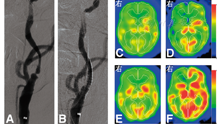

部分动脉血管性疾病引起的慢性灌注障碍患者处于非常危险的状态,故需血管外科手术。血管成像技术(如血管造影术)可以检测动脉闭塞或狭窄,并识别其侧支循环,但不能提供血液供应等代谢信息。只测量CBF存在明显不足,因为当脑血流灌注压降低时,其可代偿性舒张血管而保持正常的脑血流量。检测动脉阻塞的血流动力学和代谢改变的方法(尤其是颈动脉血流的改变),包括在基线测量CBF和应用血管扩张刺激剂后测量CBF(图6),因损害而增加的CBF表示减少的脑灌注压力;CBV和CBF的定量测量都在静息状态下进行,CBV/CBF比值增加表明血流动力学紊乱;测量OEF可作为局部自动调节功能是否正常的指标。在这些测量方法的基础上,学者[45,77]提出了血流动力学改变的3个阶段:0期,侧支循环完全弥补了动脉闭塞;Ⅰ期(血流动力学紊乱),其中CBV增加,但血管扩张刺激的CBF减小,OEF保持正常;Ⅱ期(血流动力学中断),CBF减少和OEF增加而保持CMRO2正常,以维持脑组织的代谢需求。OEF的异常改变可作为预测同侧后续脑卒中的指标之一[78]。在颈动脉支架置入术前和术后进行PET显像,可发现CBF、脑灌注压和CMRO2得到改善[79],SPECT显像血流动力学稳定(图6)[80],在双侧颈动脉疾病中也是如此[81]。代谢储备的降低可导致皮质神经元的丢失,这不能通过CT或MRI的形态学成像检测,但可通过123I-碘西尼SPECT[53]或11C-氟马西尼PET[82]发现。尽管部分患者存在这一阶段,但颅外-颅内搭桥手术并没有降低缺血性脑卒中患者在2年内复发的危险性,因为在围手术期脑卒中的发病率较高而抵消了长期受益[83]。